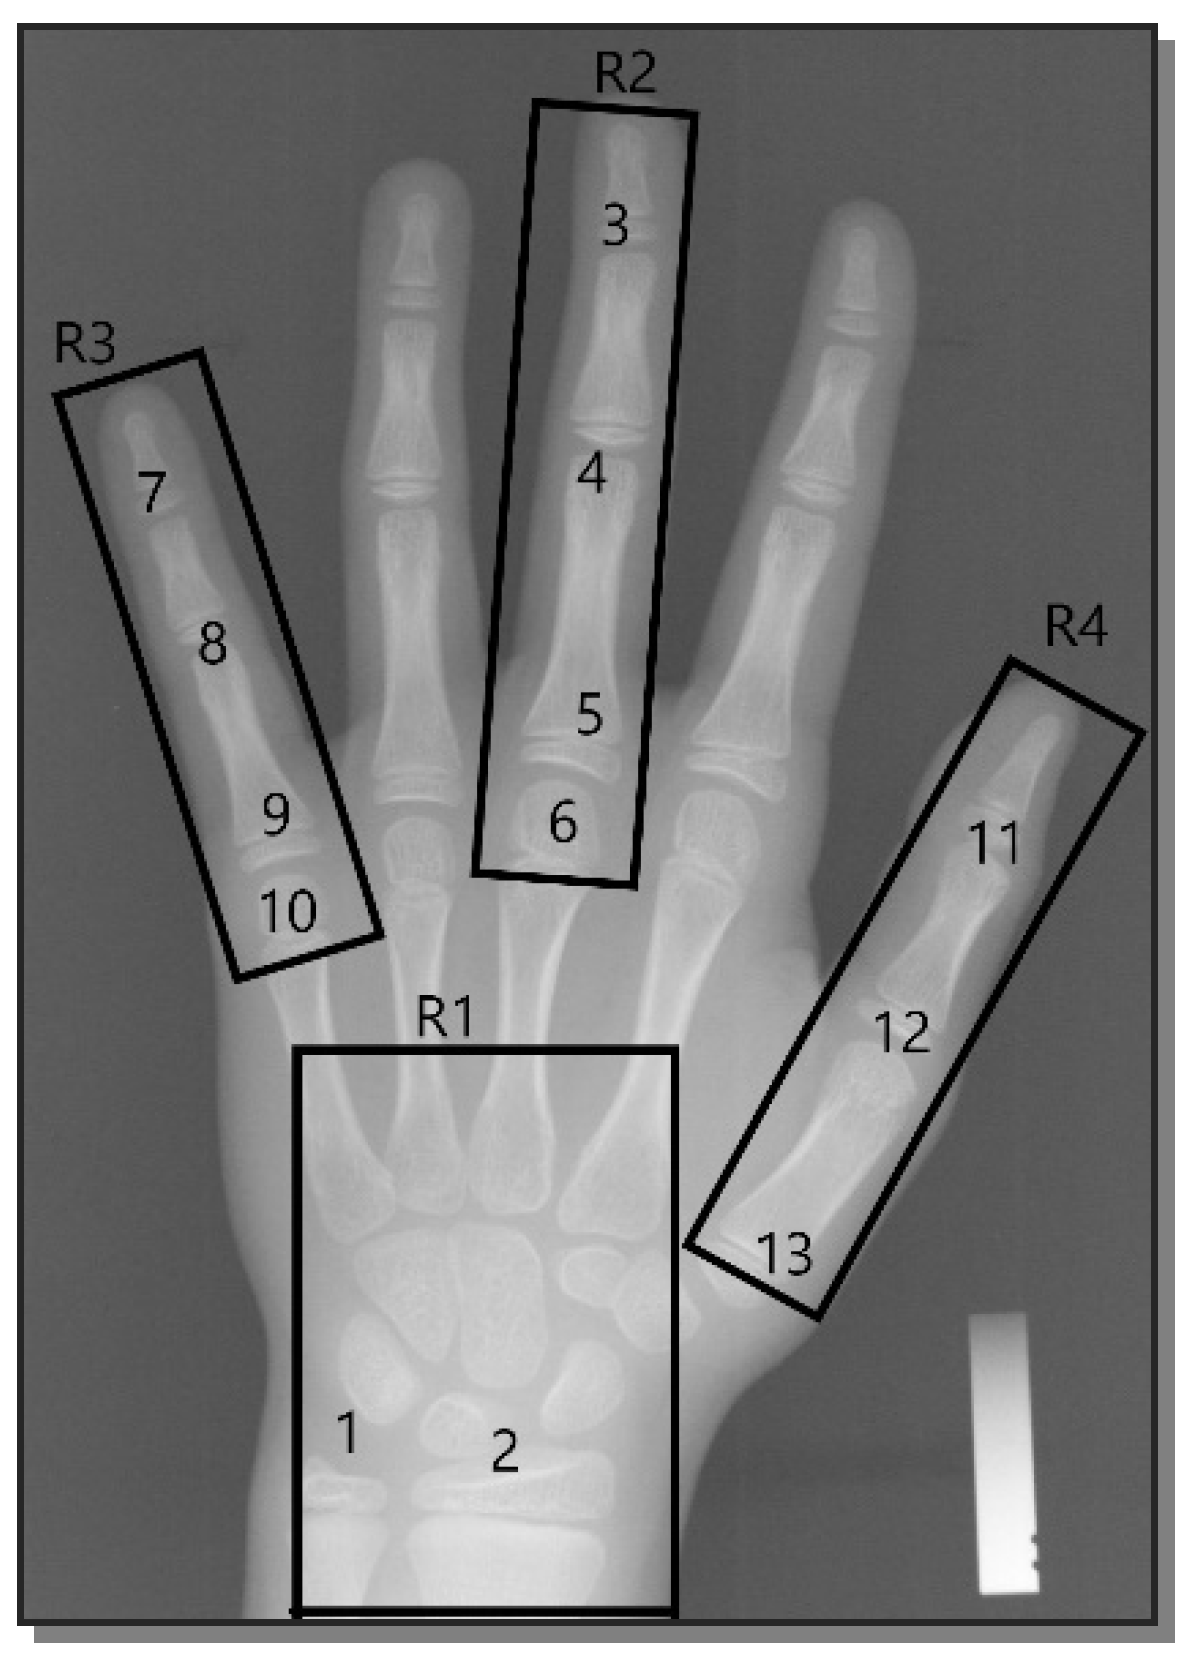

3.2. Extraction of ROI Regions